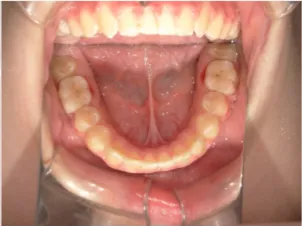

治療後⑤中2:治療終了

| 治療期間 | 小5~中2 |

| おおよその費用 | 矯正治療費:1,034,000円 |